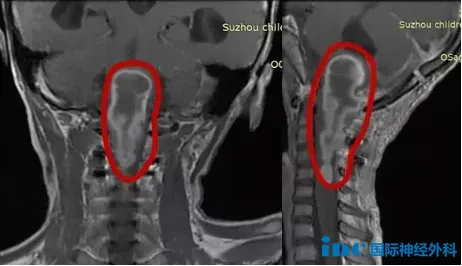

6岁确诊脑干胶质瘤,曾无法手术的他,如今竟已安稳步入中年!

一个孩子的健康成长需要付出多大的努力?自从6岁的儿子被确诊为脑干胶质瘤,这一家人足足抗争了29年。29年,他们目睹了神经外科的发展,也见证了儿子身上发生的奇迹。这是独属于一家人...